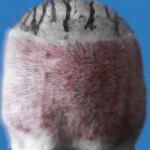

| INFECCIONES TERRIBLES | COMPLICACIONES POTENCIALMENTE MORTALES | RESULTADOS HORRIBLES |